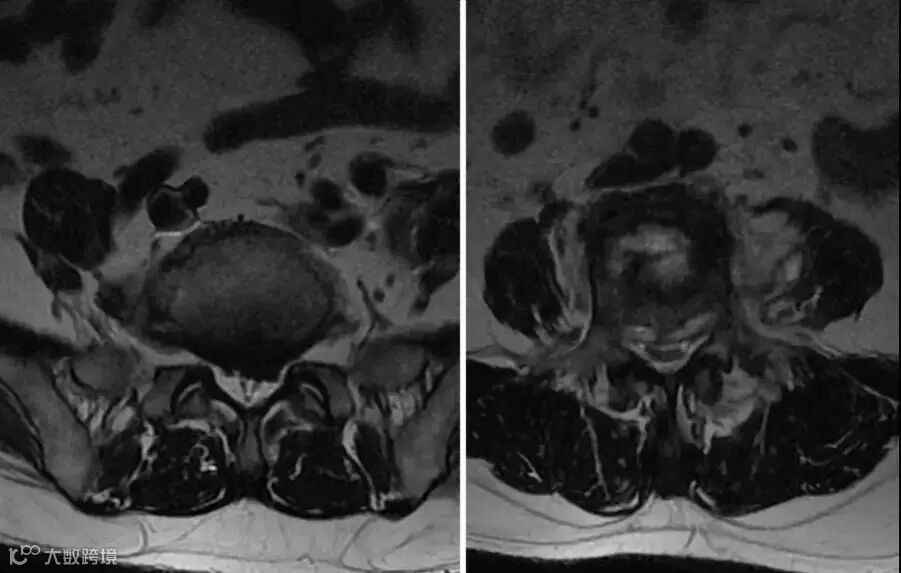

【术前核磁共振】

我院骨科主任王立胜主刀,为石某实施全身麻醉,然后行腰4椎体爆裂性陈旧性骨折后路半椎板切除椎管减压+腰3、4椎间CAGE融合植骨+椎弓根钉棒内固定术。手术效果良好,石某卧床休息两周后即可佩戴支具下地行走。